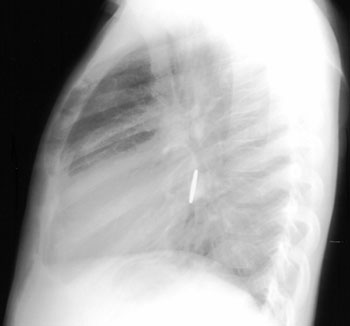

Lateral view of coin

Coin in midthoracic esophagus

Most swallowed foreign bodies, especially the round ones, pass through the entire gastrointestinal tract successfully, but some lodge in the esophagus, usually proximally at the thoracic inlet or at the level of the aortic arch. The most common foreign body is a coin. Batteries can cause mucosal damage. The treatment is endoscopic removal or fluoroscopically guided removal. Complications of chronic foreign bodies include traumatic tracheoesophageal fistula or an inflamed mass that compresses the trachea resulting in respiratory symptoms. On XR, a coin lodged in the esophagus has its widest dimension on the AP view and a coin in the trachea has its widest dimension on the lateral view.